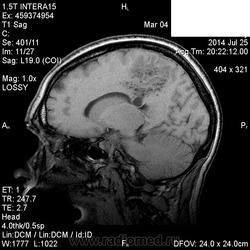

Мама приятельницы.Нарушение походки в течение 2-3 месяцев.

DDs: рассеянный склероз, токсоплазмоз, mts.

Рассеянный склероз вряд ли. Я бы добавила лимфому и глиобластому.

Думается больше о глиобластоме в форме бабочки. Из книги "Диагностическая нейрорадиология". Корниенко, Пронин.

На РС точно не похоже. Токсоплазмоз - навряд ли, т.к. "мама приятельницы", а это чаще всего бывает у ВИЧ-инфицированных.

+1 к глиобластоме.

Да, больше данных за опухоль.

Сегодня узнала: нейрохирурги за лимфому.Сделали КТ и подтвердили .

КТ-перфузию, наверное, делали? А CBV, CBF, MTT не знаете сколько было? При лимфоме CBF будет снижен, MTT выше, а накопление контраста интенсивное на постконтрасте, сканы бы и карты глянуть, если есть возможность. Что уж, похожи эти две " бяки" и очаговостью и кольцевидным типом накопления контраста и наличием некроза, кт перфузия, конечно, добавит информации. Стереотоксическую биопсию не будут делать? Лечение=химия+лучи, операция малоэффективна. Все равно- печалька.